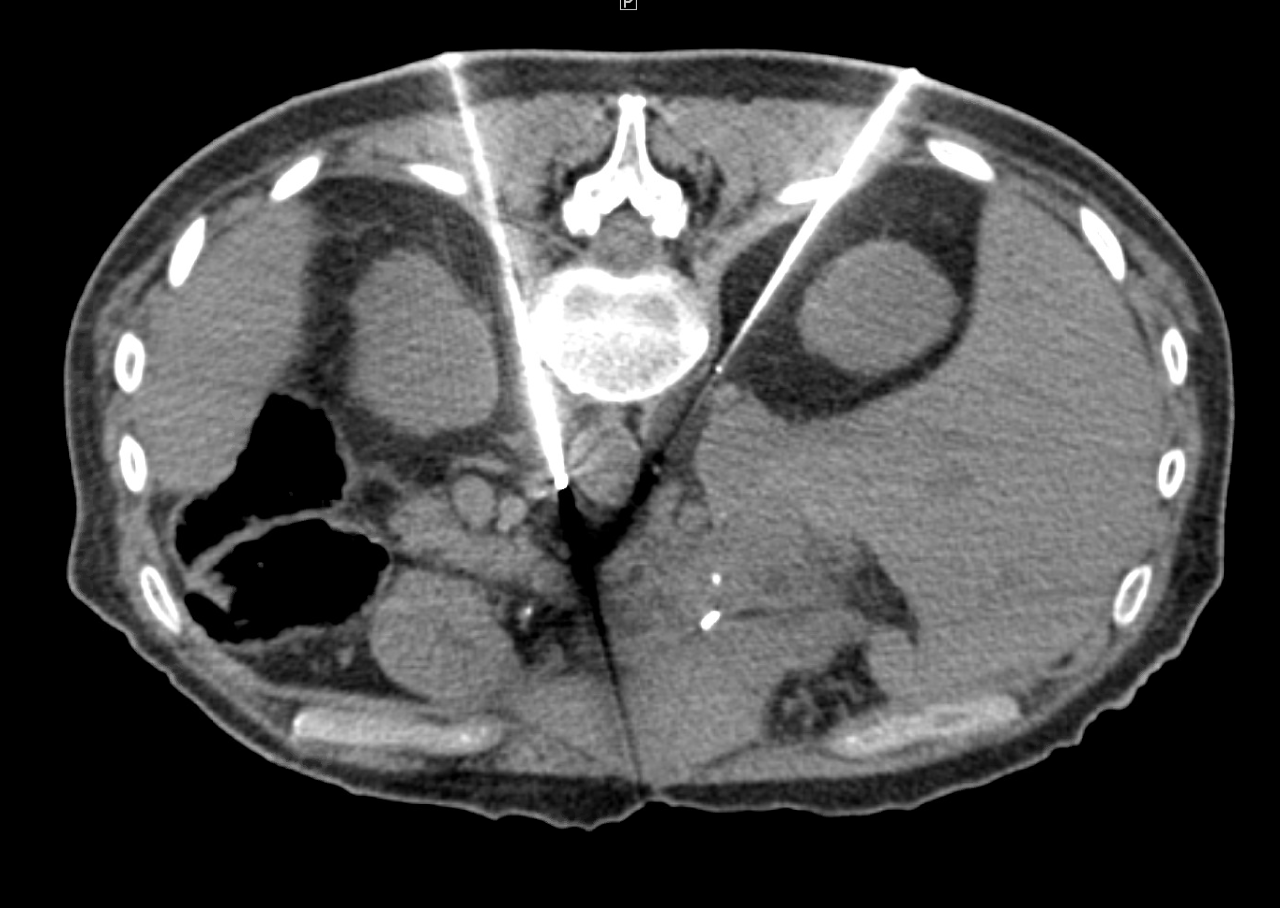

Treatment of lesion adjacent to colon Treatment of lesion adjacent to colon

Adjacent Structures and RCC

A 66-year-old man presented with 2.0 cm x 2.1 cm left sided, endophytic RCC and biopsy confirmed clear cell renal cell carcinoma. Initial CR images on the day of the procedure demonstrated the lesion and adjacent colon, which would likely be injured if not moved. Cryoablation was performed with three IceRod™ 1.5 CX Needles for treatment and a yueh needle was utilized to introduce normal saline to hydrodissect away the adjacent colon. The patient had no pain or significant complaints; he was discharged and returned to work the same day of the procedure. He continues to be without evidence of residual/recurrent disease one-year later.

Shamar Young, MD I University of Minnesota I Minneapolis, MN